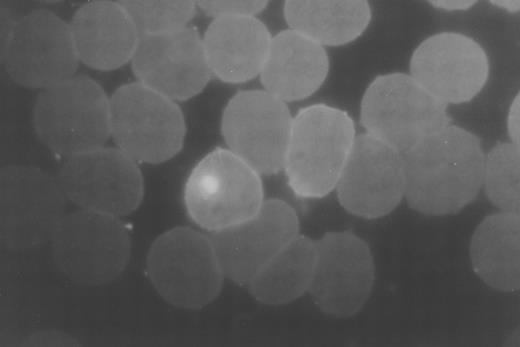

Immunofluorescence photomicrograph (original magnification × 1,000) stained with ethidium bromide and FITC-conjugated anti-RESA demonstrating a parasitized RBC on the left and a RESA positive, parasite negative RBC on the right.

Acute malaria.Of the 48 patients studied, 26 had severe falciparum malaria (12 cerebral malaria, 3 acute renal failure, 1 severe anemia, 2 jaundice, 8 hyperparasitemia) and the other 22 had uncomplicated malaria. Four patients with severe malaria (15%) died. The geometric mean (range) parasite counts were higher in the severe malaria group; 174,830/μL (3,010 to 1,210,920) compared with the uncomplicated group; 26,540/μL (2,070 to 221,560); P < .05. The mean (standard deviation [SD]) hematocrit was similar in the severe and uncomplicated malaria groups; 32 (9)% and 35 (8)%, respectively. The clinical and laboratory values for the patients with severe malaria are shown in Table 1. Thin blood films from malaria patients on admission that contained bright ethidium bromide-stained parasite nucleic acid were then stained with the pooled immune sera or MoAb 33G2 and showed the typical RESA pattern of staining on the infected RBCs. This pattern was also seen on some uninfected RBCs (RESA-RBC) containing no ethidium bromide (Fig 1). The absolute number of RESA-RBC was higher in patients with severe malaria (geometric mean [range] 21,720/μL [5,650 to 166,550] compared with 7,200/μL [2,390 to 39,190] in patients with uncomplicated malaria. The median (range) ratio of parasitized RBCs to RESA-RBCs was 8.63 (0.133 to 50) for severe patients and 2.917 (0.278 to 20) for uncomplicated patients (P < .05). There was a significant positive correlation between absolute parasitemia and absolute RESA-RBC numbers (r2 = .52, P = .0004), ie, RESA-RBC accounted for 50% of the variation of parasitemia (Fig 2). There were no significant correlations for any other markers of disease severity including spleen size, hematocrit, lactate, or glucose.1 7 There was no significant difference for duration of previous illness before presentation or for outcome.